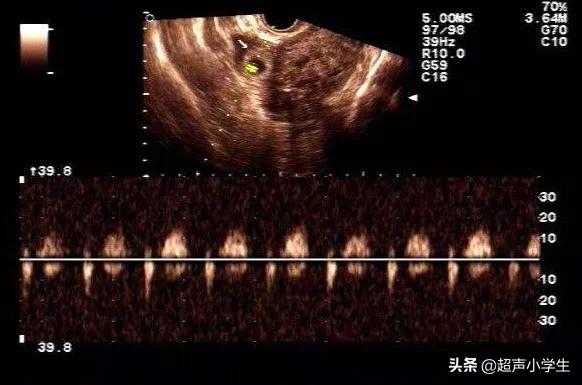

Il est préférable de procéder à une échographie pour vérifier si le bébé est à 7 semaines de grossesse, et si l'échographie est négative, vous pouvez déjà voir les bourgeons et le cœur du fœtus, donc tant que le fœtus est normal à l'échographie, il n'y aura pas de problème. Cela déterminera la sécurité du bébé.

C'est le meilleur moment pour se rendre à l'hôpital pour un test de maternité. À 7 semaines de grossesse, l'embryon a déjà été pondu et le cœur du fœtus est présent, de sorte que vous pouvez déterminer si le fœtus se développe normalement grâce à l'échographie. En outre, des analyses de sang peuvent également être effectuées pour confirmer les niveaux d'hormones et déterminer si la grossesse est normale.

Pour réaliser une échographie abdominale, vous devez boire de l'eau et retenir vos urines, mais il n'est pas nécessaire d'être à jeun.

Vérifiez la taille et la position du sac gestationnel, qui est normal s'il est de la bonne taille et positionné dans l'utérus. À 7 semaines, le fœtus mesure 1,33 cm de long et le diamètre du sac gestationnel est supérieur à 2 cm et occupe un tiers de la cavité utérine.

Si vous avez subi une césarienne, vous devez également veiller à ce que le sac gestationnel soit éloigné de la cicatrice ; trop près ou sur la cicatrice peut être plus dangereux.

L'échographie permet également de déterminer la taille des bourgeons, qui mesurent 9,3 mm de long à 7 semaines, pour voir s'ils sont normaux et, s'ils ne correspondent pas exactement, ils peuvent être utilisés pour calculer la semaine de grossesse correcte. C'est également le moment de vérifier le cœur du fœtus. S'il y a déjà un battement de cœur primitif, c'est normal.

Lorsque vous êtes enceinte de 7 semaines, vous pouvez vérifier les battements de cœur et les bourgeons du fœtus et observer votre taux de HCG et de progestérone. S'il y a déjà un cœur et des bourgeons fœtaux, que la position de l'embryon n'est pas proche de l'embouchure de l'utérus et que les autres indicateurs sont normaux, vous pouvez vous sentir à l'aise avec votre grossesse. À ce stade, vous devez veiller à prendre des suppléments d'acide folique et de vitamines, ne pas boire beaucoup de thé et de café, et faire attention à ne pas avoir trop de pression sur l'abdomen, ne pas prendre de médicaments à volonté, être rassurée sur l'humeur, et être à l'heure pour les examens de maternité peuvent être.

Au début de la grossesse, le taux de progestérone doit être supérieur à 20 ou plus ; un faible taux de progestérone augmente la probabilité d'une fausse couche. Passez une échographie pour rechercher des germes, le cœur du fœtus et tout signe de saignement.Si la valeur de la progestérone est normale, l'échographie révèle un germe, un cœur fœtal et aucune autre anomalie. Un tel bébé est sans danger.

Deuxièmement, l'échographie abdominale

Les battements du cœur du fœtus peuvent être entendus à l'échographie vers la 7e semaine et ont un rythme distinct. Si vous êtes vraiment inquiète, vous pouvez essayer.

Le médecin m'a dit d'aller faire un nouveau contrôle dans 10 jours, j'y suis allée le 10ème jour, et il y avait un bourgeon et un cœur, et mon cœur s'est instantanément détendu, vous voulez vous assurer que votre bébé est en sécurité ou non, vous feriez mieux d'aller à l'hôpital pour une échographie, le contrôle nécessite de retenir votre urine. Si tout va bien, à 8 semaines, vérifiez les bourgeons fœtaux et le cœur fœtal, certains développements sont lents, les bourgeons fœtaux et le cœur fœtal ne sont pas si rapides.

Il n'y a en principe aucun signe d'interruption de grossesse dans les premiers stades, et ce n'est que lorsque nous passons une échographie et que nous constatons qu'il n'y a pas de battements de cœur ou de bourgeons fœtaux après que l'embryon a dépassé 60 jours que nous pouvons en principe déterminer qu'il s'agit d'une interruption de grossesse.

Il faut rechercher les bourgeons fœtaux et le rythme cardiaque du fœtus, et dans un peu plus de deux mois, il faut faire une échographie et entendre le son du cœur du fœtus qui bat, ce qui est incroyable !